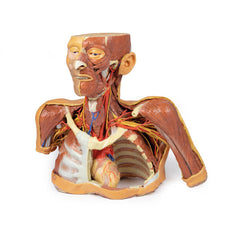

3D Printed Superficial Facial Nerves & Parotid Gland

This 3D model presents the superficial anatomy of the face and head, and compliments the superficial facial anatomy

of our HW 44 model with a more expanded dissection across the scalp and occipital regions.

The superficial

neurovascular and muscular structures in the face largely mirror the structures described in reference to our HW 44

specimen (see description), although the terminal branches of the facial nerve (CNVII) can be largely followed

across a longer course from the parotid gland and the platysma muscle has been retained superficial to the mandible

and extends towards the neck.

In contrast to the HW 44 specimen, this model has a more expansive superficial

dissection inferior to the external ear and across the posterior scalp and occipital region. This allows for an

expanded appreciation of the neurovascular distribution of the supraorbital and supratrochlear nerves and arties

with the superficial temporal artery. Inferior to the ear, the retromandibular vein has been exposed with the

ascending fibres of the great auricular nerve on its superficial surface (and further branches of this nerve on the

surface of the sternocleidomastoid muscle). At the posterior border of the sternocleidomastoid muscle the lesser

occipital nerve is just preserved, near the exiting and ascension of the occipital artery and vein near the

trapezius muscle towards the posterior scalp. Surrounding the external ear are fibres of the auricularis superior

and posterior muscles. Near the margin of the dissection window posteriorly the deep fibres of the occiptalis muscle

can be seen integrated into the epicranius (occipitofrontalis) muscle.